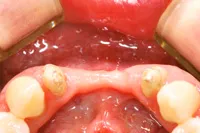

インプラント義歯

(ミニインプラント)

現在、総入れ歯を使っている方で、「入れ歯が動いて不快感のある方」「硬いものや、ひっつくものを普通に食べてみたい方」「入れ歯が落ちたり動くのを気にしないで、思いっきり会話をしたり、笑ってみたい方」にお勧めするのが、「インプラント義歯(MDIミニインプラント)」と呼ばれるものです。

インプラント義歯とは、通常のインプラントに比べてかなり細いインプラントを埋め込み、それを固定源として入れ歯を安定させる治療法です。

歯茎を切開せずにインプラントを埋め込みますので、ほとんど痛みも抑えられ短時間で治療が終了します。そのため、高齢者の方にも負担がかからないので安心して治療を受けて頂くことができます。